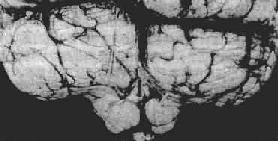

3.小脑扁桃体疝又称枕骨大孔疝。主要由于颅内高压或后颅凹占位性病变将小脑和延髓推向枕骨大孔并向下移位而形成小脑扁桃体疝。疝入枕骨大孔的小脑扁桃体和延髓成圆锥形,其腹侧出现枕骨大孔压迹(图16-8),由于延髓受压,生命中枢及网状结构受损,严重时可引起呼吸变慢甚至骤停,接着心脏停搏而猝死。

小脑扁桃体疝

图16-8 小脑扁桃体疝

示小脑切迹,两侧扁桃体疝形成